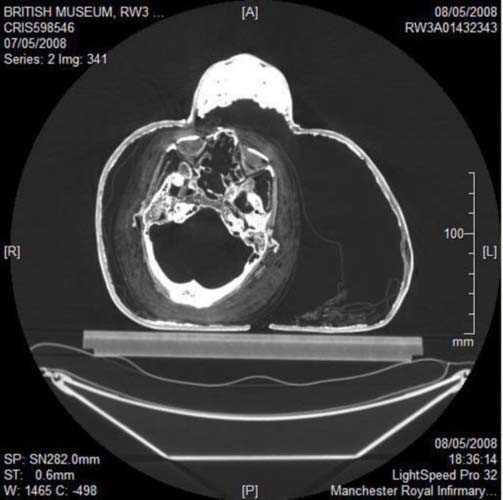

2. Fotoğrafta gördüğünüz Mısır mumyasının CT taraması, uygarlığının gizemlerini çözmeye yardımcı olacak.

Fotoğrafta gördüğünüz Mısır mumyasının CT taraması, uygarlığının gizemlerini çözmeye yardımcı olacak.

3. İngiltere'de Dr. Abeer Helmi, bu teknolojiyi kullanarak tarihin derinliklerinden gelen lahitleri açarken zarar verme riski olmadan içeriğini görüntüleyebiliyor.

İngiltere'de Dr. Abeer Helmi, bu teknolojiyi kullanarak tarihin derinliklerinden gelen lahitleri açarken zarar verme riski olmadan içeriğini görüntüleyebiliyor.

4. Dr. Helmi, British Museum'dan özel izinle aldığı yedi mumya üzerinde bu cihazı test etti.

Dr. Helmi, British Museum'dan özel izinle aldığı yedi mumya üzerinde bu cihazı test etti.